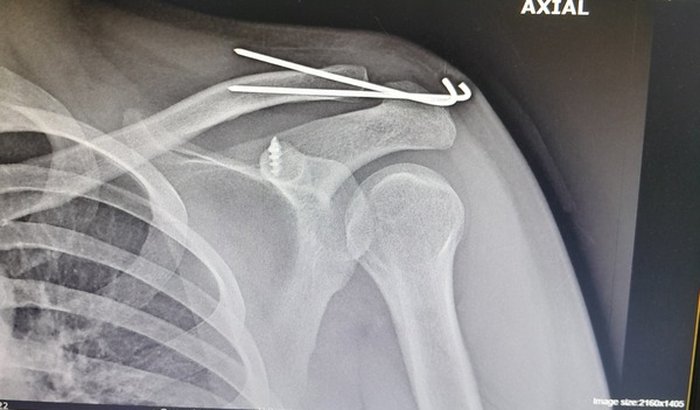

Me chamo Luan, criei essa vaquinha para juntar dinheiro para despesas de casa, sofri um acidente de moto, onde tive que passar por procedimento cirúrgico no ombro, impossibilitando de trabalhar ou fazer qualquer movimento com os braços, por conta disso não posso trabalhar por alguns meses e preciso de ajuda para minhas despesas.